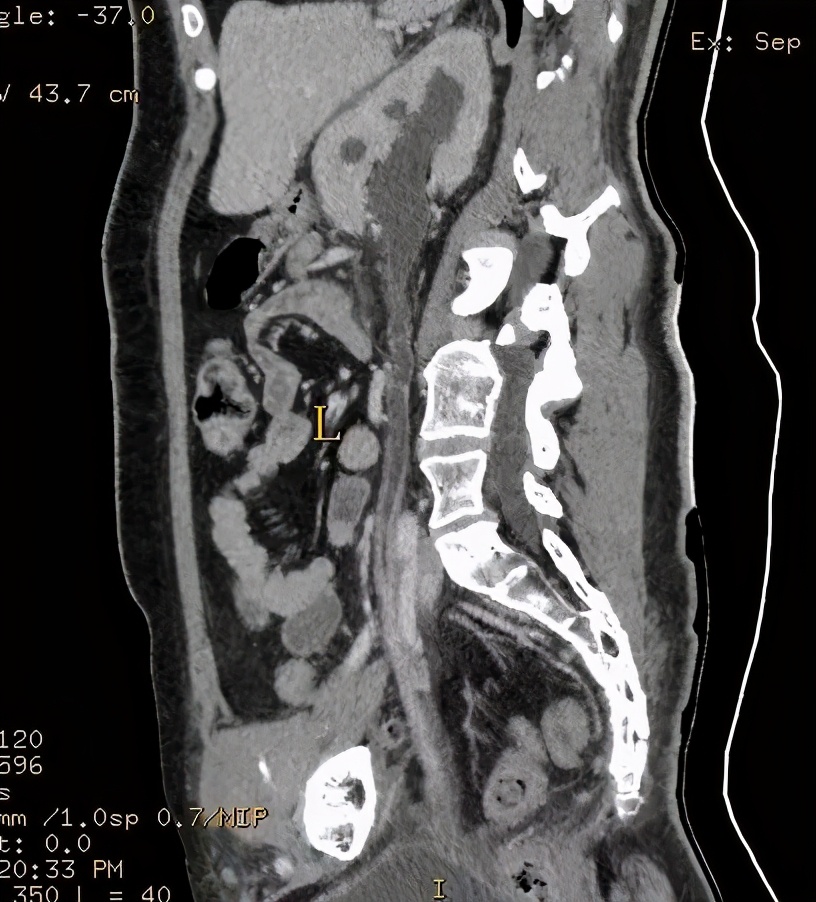

上图所示:63岁男患,有脑出血术后病史,长期卧床,近期存在小便*禁失**。CT尿路造影检查示膀胱壁增厚,存在膀胱憩室,伴有双肾积水,双侧输尿管扩张。考虑存在神经源性膀胱可能